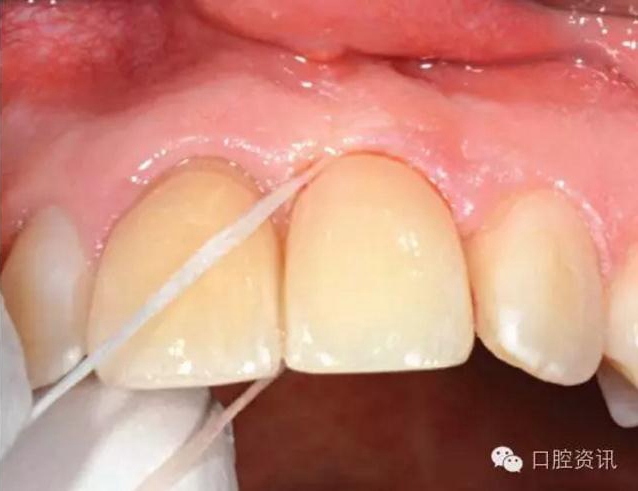

8. 種植牙和真牙看上去一模一樣嗎?

種植牙義齒可以代替單顆牙齒、連續(xù)多顆牙齒或者整排牙齒。正確的

植入和修復會使種植牙呈現(xiàn)令人滿意的美觀效果。目前, 先進的臨床

技術(shù)和材料已經(jīng)可以讓種植牙修復達到令人滿意的美學效果。一般情

況下,是看不出來種植牙和真牙的區(qū)別的,真假難辨。

牙醫(yī)會根據(jù)您本身的條件重建和美化口腔。您本身的條件一般指植體

周圍骨和軟組織的質(zhì)、量。有一些軟組織不足( 例如, 牙齦缺損 ) 的病

例可能需要軟組織移植 ( 例如, 從上腭取一塊黏膜) 來獲得理想的美

觀效果, 有一些病例可能只有降低美觀要求才能達到更好的修復效

17.jpg

圖 17. 種植牙修復單顆前牙缺失